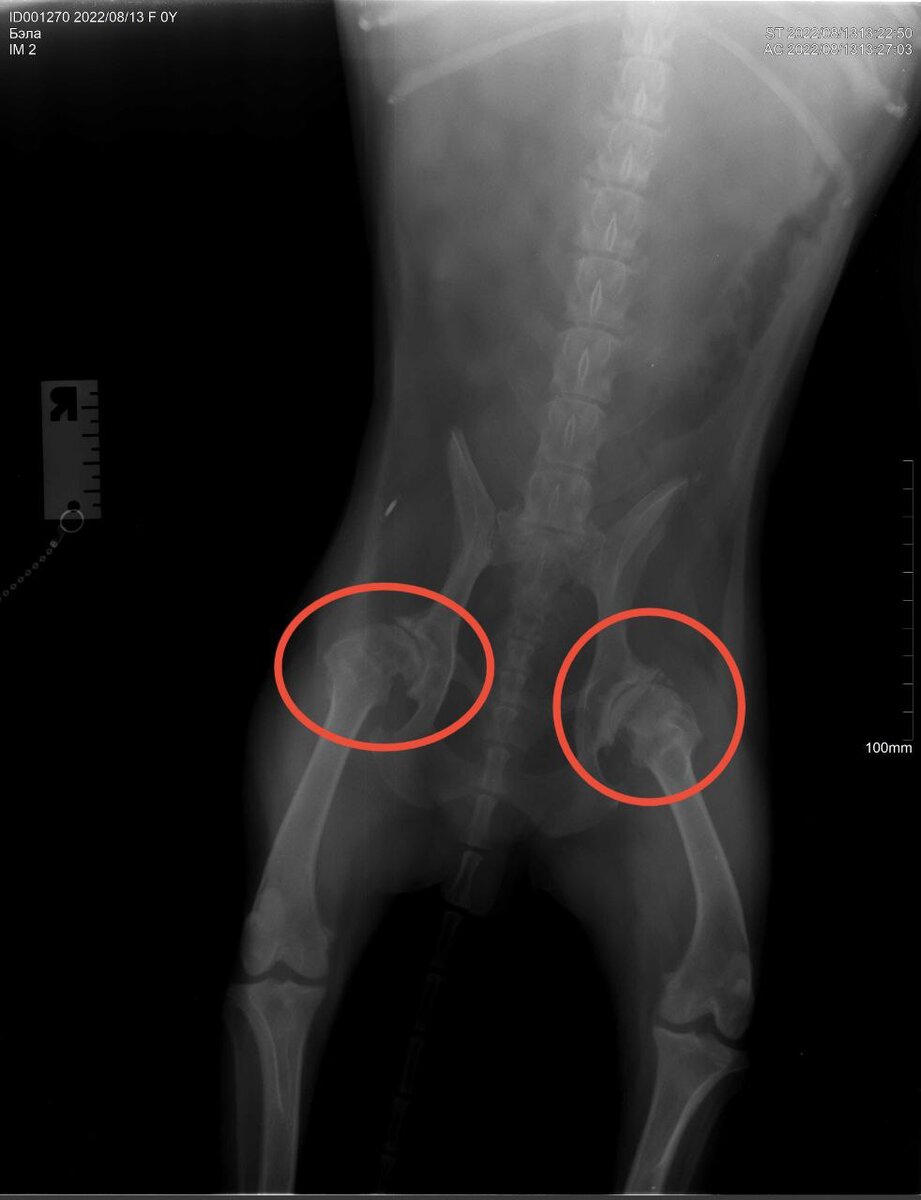

Дикушка Бэла и её проблемы с позвоночником

На днях я возил Бэлу в клинику, потому что у неё начались проблемы с задними лапами. Как выяснилось, срослись позвонки и стёрлись суставы в тазобедренном, из-за чего она стала плохо ходить и заваливаться.

Вариантов лечения, как таковых, немного: всё сводится к пожизненному приёму обезболивающего. Собака в возрасте, диковатая, а значит сложные операции с последующей долгой реабилитацией проводить затруднительно и опасно. Длительный приём обезболивающего же имеет свойство негативно влиять на почки и печень — нам это тоже не подходит. Здравое решение из всех допустимых я нашёл в гомеопатии.